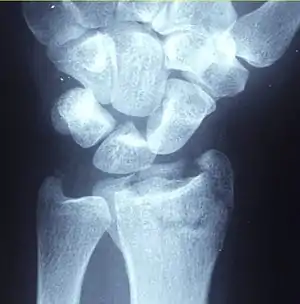

Distal radius fracture

A distal radius fracture, also known as wrist fracture, is a break of the part of the radius bone which is close to the wrist.[1] Symptoms include pain, bruising, and rapid-onset swelling.[1] The ulna bone may also be broken.[1]

| A Colles fracture as seen on X-ray: It is a type of distal radius fracture. | |